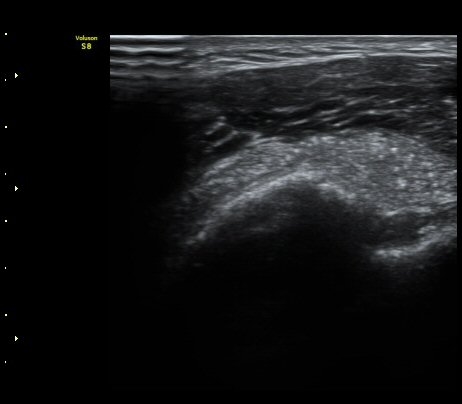

À̵ιڱ٠Ⱦ´Ü¸é°Ë»ç¿¡¼­ Á¡¾×³¶³» °í¿¡ÄÚ ¼®È¸È­ À½¿µµéÀÌ °üÂûµÊ(±×¸² 1, 2, 5)

¿ÜȸÀüÀÇ Á¦ÇÑÀ¸·Î °ß°©ÇϱٰÇÀÌ ¼öÆòÀ¸·Î °üÂûµÇÁö ¸øÇϰí À̵ιڱ٠ǥÃþ¿¡

¼®È¸È­ À½¿µÀÌ °üÂûµÊ(±×¸² 3)